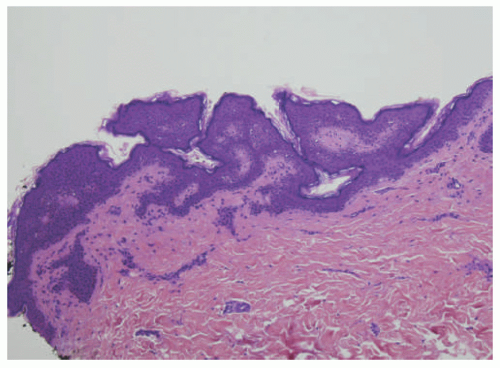

![]() FIGURE 23-3. Inflammatory linear verrucous epidermal nevus (ILVEN) presents as an erythematous and scaly linear plaque, resembling linear psoriasis. |